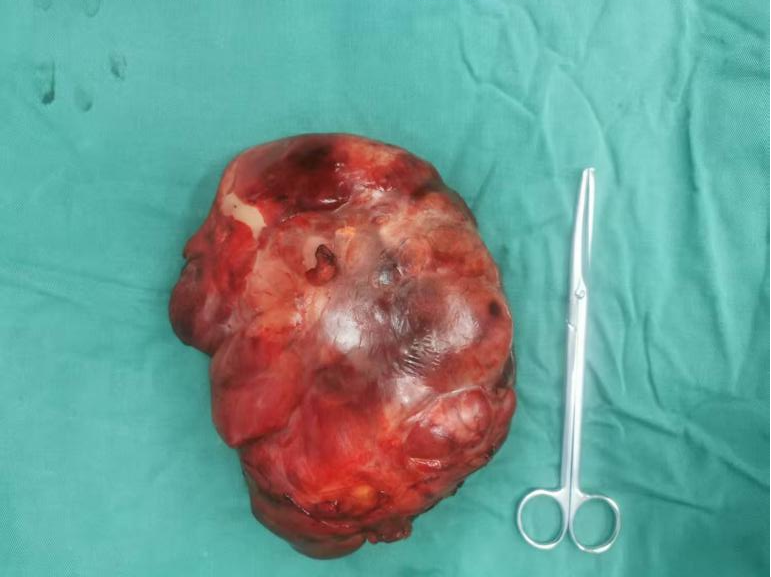

手术由胃肠(肛肠、疝)外科汪勇副主任医师和肝胆胰外科周宝勇副主任医师共同主刀,成功地将这个巨大的肿瘤完整切除。目前,杨阿姨的康复进程非常顺利。

被切除下来的肿瘤标本